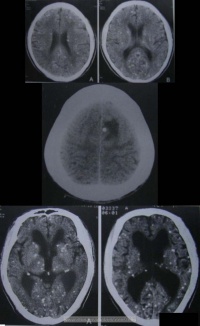

CT:

1.活动期

1)脑实质内脑囊虫大多呈圆形囊性病变,其内头节呈偏心的小点状,附在囊壁上,周围无水肿或轻度水肿,增强扫描囊壁和囊内头节可轻度强化或不强化。

2)脑室内活囊虫以第四脑室多见,呈囊状,表现为脑室扩大积水,其内可见小结节样等或高密度头节,CTM可以显示脑室内充盈缺损。

3)脑沟、脑池、脑裂活囊虫及头节表现与脑实质内活囊虫相似。

2.退变死亡期

1)脑实质内囊虫死亡,头节消失,虫体肿大变形,由于虫体死亡释放大量异体蛋白,在脑实质内引起广泛的低密度脑水肿,有占位效应。增强扫描囊壁明显强化,可呈环状强化或结节状强化,强化环的厚度较囊虫活动期明显增宽。囊内低密度代表囊虫向纤维化和机化过渡。

2)脑室系统内囊虫死亡后,除头节消失,虫体胀大外。囊体增大可引起占位效应。

3.非活动期囊虫死亡后发生钙化,CT呈点状高密度钙化灶。位于蛛网膜下隙者引起蛛网膜肥厚、粘连,可伴有脑积水。

4.混杂期活动期、退变死亡期、非活动期的囊虫混杂存在。